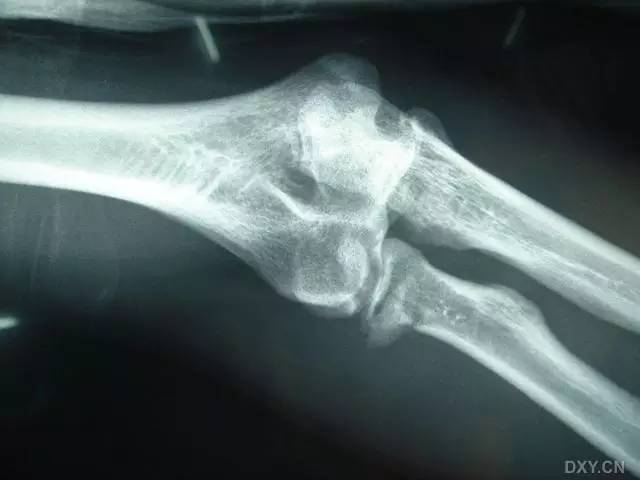

全肱骨小头骨折,为一种少见的关节内骨折,多见于成年人。常由于跌倒时手过度伸直或在屈肘时因桡骨小头撞击肱骨小头,并同时有外翻力存在时发病,亦可伴有滑车骨折与内侧副韧带的撕裂。X 线表现为全肱骨头骨折,向上移位。

Hahn-steinthal 骨折 X 片(来源:Hahn-Steinthal fracture: a case report.BioMed central Cases Journal20081:239)